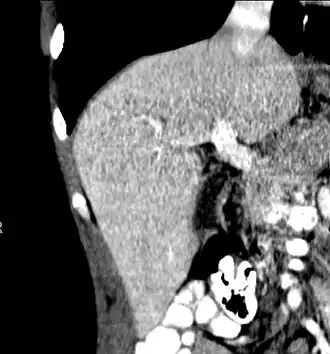

The diagnosis of liver disease is made by liver function tests, groups of blood tests, that can readily show the extent of liver damage. If infection is suspected, then other serological tests will be carried out. A physical examination of the liver can only reveal its size and any tenderness, and some form of imaging such as an ultrasound or CT scan may also be needed.

A CT scan in which the liver and portal vein are shown